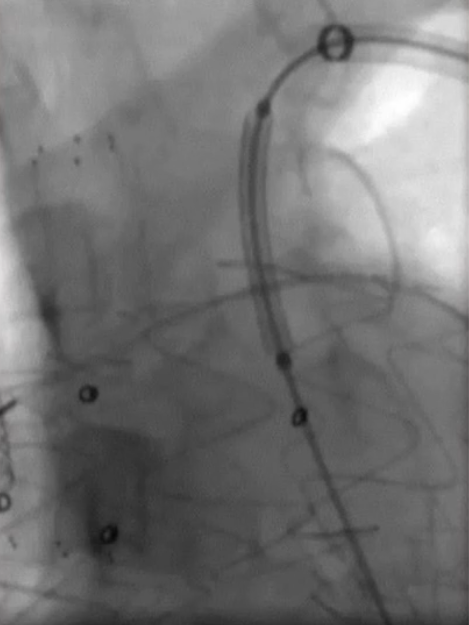

先后导入4mm、6mm和8mm球囊对覆膜区进行扩张。考虑到患者颈总动脉存在较严重的动脉硬化,为避免置入大血管鞘带来的风险,选择使用10-40mm自膨式裸支架重建左颈总动脉,使用10-60mm球囊进行后扩张。扩张后,支架形态满意,成功恢复了左侧颈总动脉血流。

更换MUSTANG 8-40mm球囊进一步扩张开窗处(图2)

★ 左锁骨下动脉重建

从左侧肱动脉导入可调弯鞘送至左锁骨下动脉近端,同样使用asahi treasure 12导丝和支撑导管顺利通过覆膜区。依次送入4mm、6mm和8mm球囊对局部进行扩张。